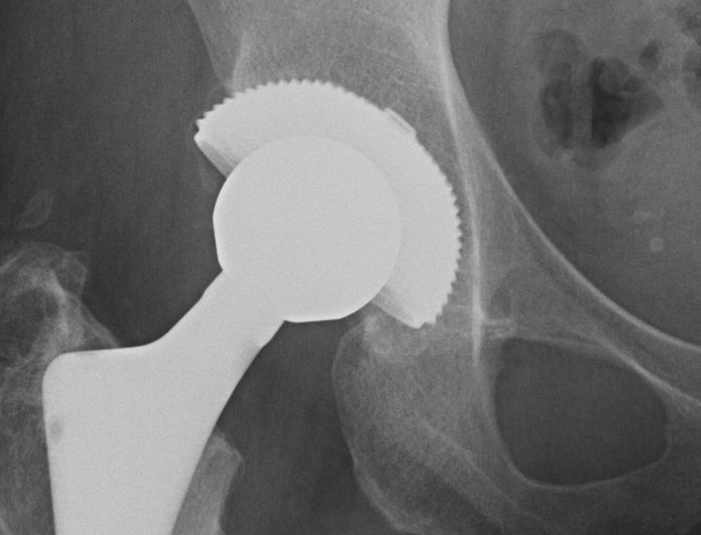

THR Uncemented Cup Superolateral Buttress 2

Radiographic signs of loosening

5 signs

- radiolucent lines that appear after two years

- progression of radiolucent lines after two years

- radiolucent lines in all three zones

- radiolucent lines 2 mm or wider in any zone

- migration > 2mm

Loose Uncemented CupLoose Uncemented Cup 2